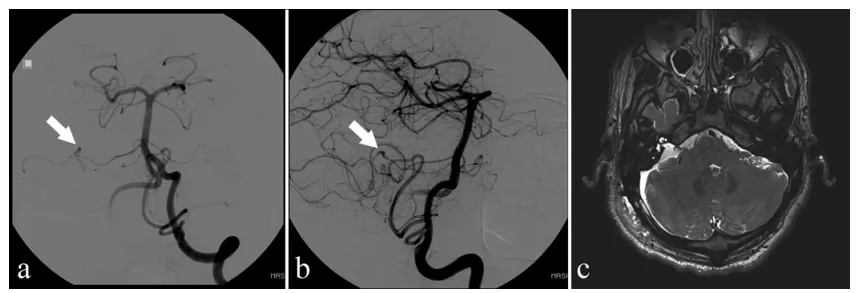

图2. 术后影像学评估结果:(a)与(b)为数字减影血管造影图像:清晰显示吻合口通畅,再吻合血管充盈良好,未见显著狭窄。(c)为MRI图像:显示吻合血管充盈良好,未发现缺血性脑卒中证据。

术后数字减影血管造影与磁共振成像检查均显示小脑前下动脉充盈良好,未见明显血管狭窄或脑卒中征象。卡尔于术后第8天顺利出院,面瘫症状完全恢复,但术前已存在的听力丧失与头痛症状持续存在。

术后一年随访复查,磁共振成像显示血管再吻合口保持通畅状态。